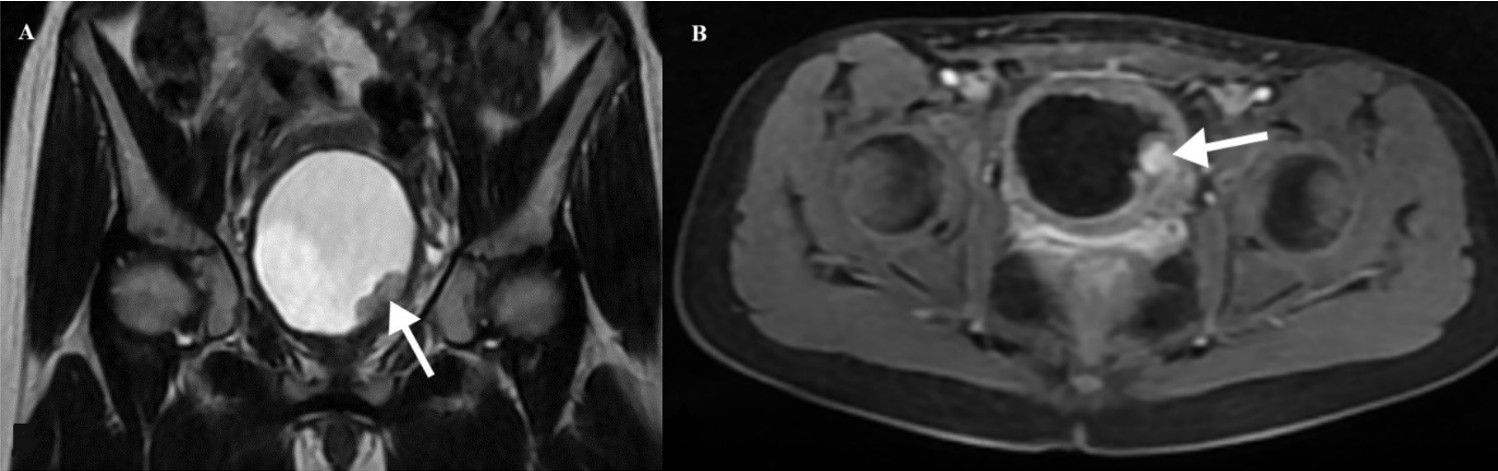

A 10-year-old girl was admitted to another hospital presenting with painless gross hematuria that led to syncope and required transfusion. Ultrasonography (US) revealed a well-circumscribed mass located at the base of the bladder. Due to uncontrollable hematuria, a palliative laparotomy was performed at another hospital. A biopsy of the bladder mass, initially suspected to represent rhabdomyosarcoma, was subsequently diagnosed as an IMT upon histopathological evaluation. The patient was then referred to our institution for further evaluation and management. The patient’s medical history was otherwise unremarkable, and both physical examination and hematologic evaluations—including complete blood count, coagulation profile, and basic serum chemistry—were within normal limits. Abdominal US showed a well-defined hypoechoic lesion measuring 30×20 mm at the bladder base, without calcification. Color Doppler imaging demonstrated mild vascularization within the lesion. Magnetic resonance imaging (MRI) revealed a contrast-enhanced solid mass measuring 20×23×30 mm in the left posterolateral bladder wall, near the bladder neck (Fig. 1). On cystoscopy, the right ureter orifice was visualized, but the left orifice was obscured by a protruding mass on the left bladder wall extending toward the bladder neck.